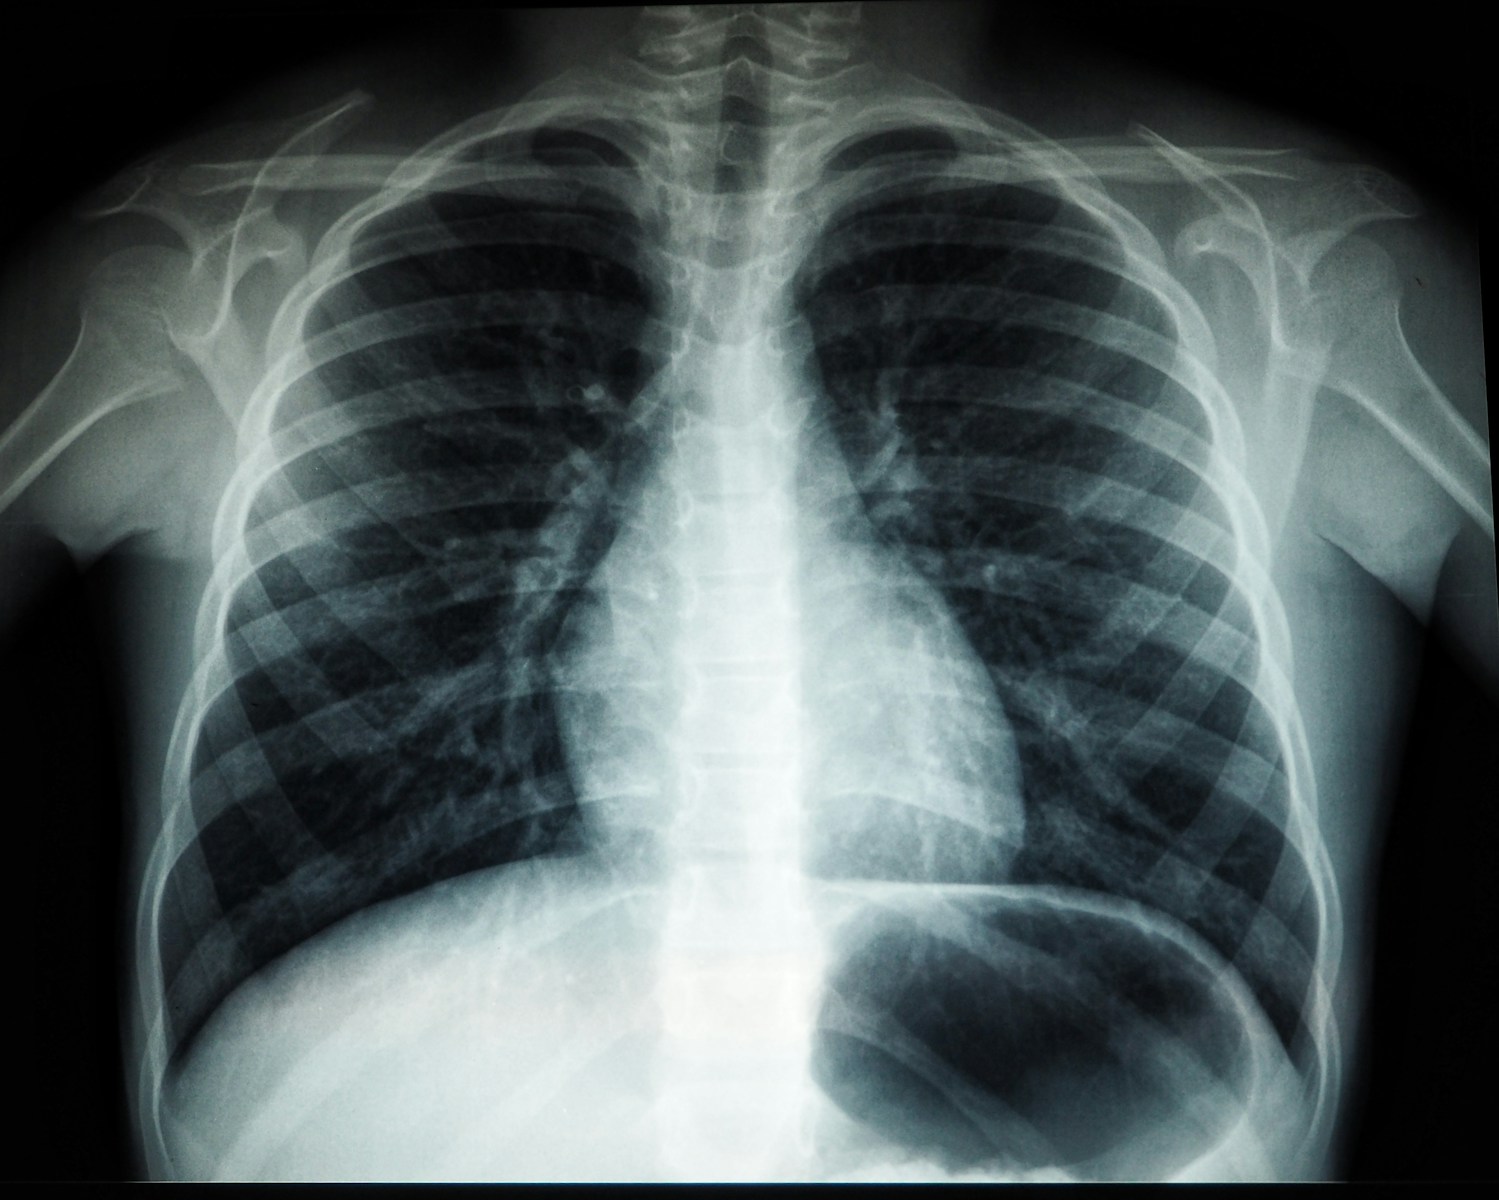

A 25-year study led by the Barcelona Institute for Global Health finds that PM2.5 increases the risk of all lung cancer subtypes, while several gaseous pollutants are associated with non-small-cell lung cancer.

Lung cancer is broadly divided into non-small-cell lung cancer, which includes adenocarcinoma, squamous cell carcinoma and large cell carcinoma, and small-cell lung cancer, a less common but more aggressive form strongly linked to smoking.

Researchers found that exposure to PM2.5 increased the risk of lung cancer across all histological subtypes. The effect was consistent regardless of whether the cancer was adenocarcinoma, squamous cell carcinoma or large cell carcinoma.